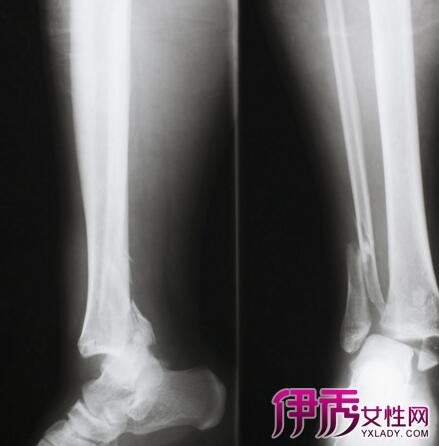

小腿粉碎性骨折属于几级伤残?如果你是在工伤中受伤,可以鉴定为九级伤残,享受本人九个月的工资补偿。如果你是在交通中受到了事故损伤,可以鉴定为二级伤残……

小腿骨折几级伤残